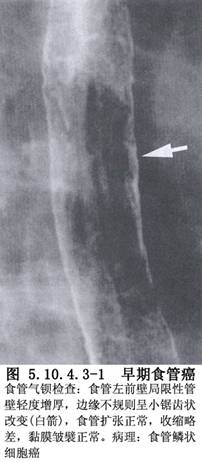

食管癌手术方法多种多样,手术途径、吻合方式、切口部位选择及体位等不尽相同,各有其优缺点。内镜技术与传统食管手术相结合的代表性手术是术VATS食管癌切除术。这种手术经胸腔镜完成胸段食管游离和淋巴结清除,经腹腔镜或腹部切口游离胃和切断食管,经颈部切口进行食管、胃吻合。VATS食管癌切除具有胸腔镜手术共同的优点,VATS食管癌切除术作为一种手术方法是可行的。但目前尚不能用VATS替代常规开胸食管癌切除手术,适应证主要局限于某些较早期的食管癌和心肺功能严重障碍不能耐受开胸手术者(图5.10.4.3-1)。

1.早期食管癌最适合胸腔镜手术(图5.10.4.3-2A~C)。